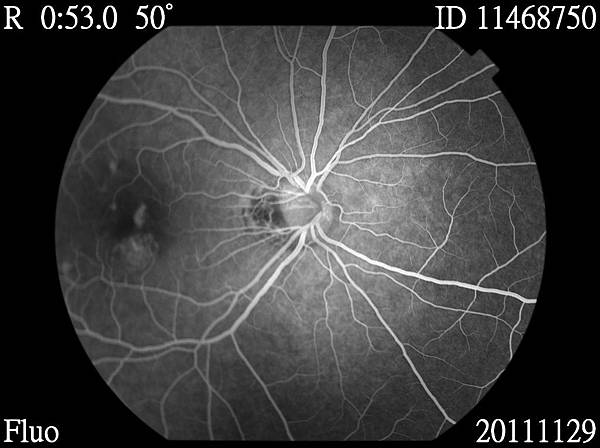

11468750_20111129_142518_Redfree_R_001.JPG 11468750_20111129_142737_Fluo_R_001.JPG 11468750_20111129_142746_Fluo_R_001.JPG 11468750_20111129_142954_Fluo_R_001.JPG 11468750_20111129_143002_Fluo_R_001.JPG 11468750_20111129_143009_Fluo_R_001.JPG 11468750_20111129_143031_Fluo_R_001.JPG 11468750_20111129_143749_Fluo_R_001.JPG 11468750_20111129_143818_Fluo_R_001.JPG

醫生說,我的黃斑部新生血管,需要眼內注射藥物去抑制他繼續增生,還有,視網膜周圍變薄了,需要先做雷射把他圍起來,避免將來破掉.....

至於新生血管的部份,要再做脈絡膜的檢查...因為我不只新生血管,旁邊還有好幾個點,這是比較奇怪的....